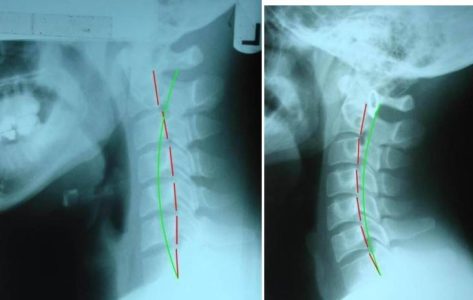

Neck-Posture-732×464-1-qqgsn8rgc7p10e49i4274gdybc6xvjduiwxjqgta0w

(Left: Straightening and reversal of the cervical lordosis, resulting in anterior head carriage. Right: Healthy neck, observe the C-shape curve allowing even distribution of pressure through the cervical spine)